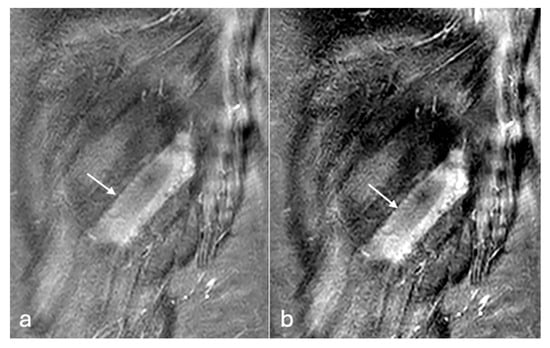

Figure 3. PDFS axial MR images of left leg (a,b). Changes in muscle oedema in tear of tibialis anterior (arrow) are better detected on the image with modified windowing (b) when compared to default windowing (a). W/L of the image (a)—1516/872, (b)—831/836.